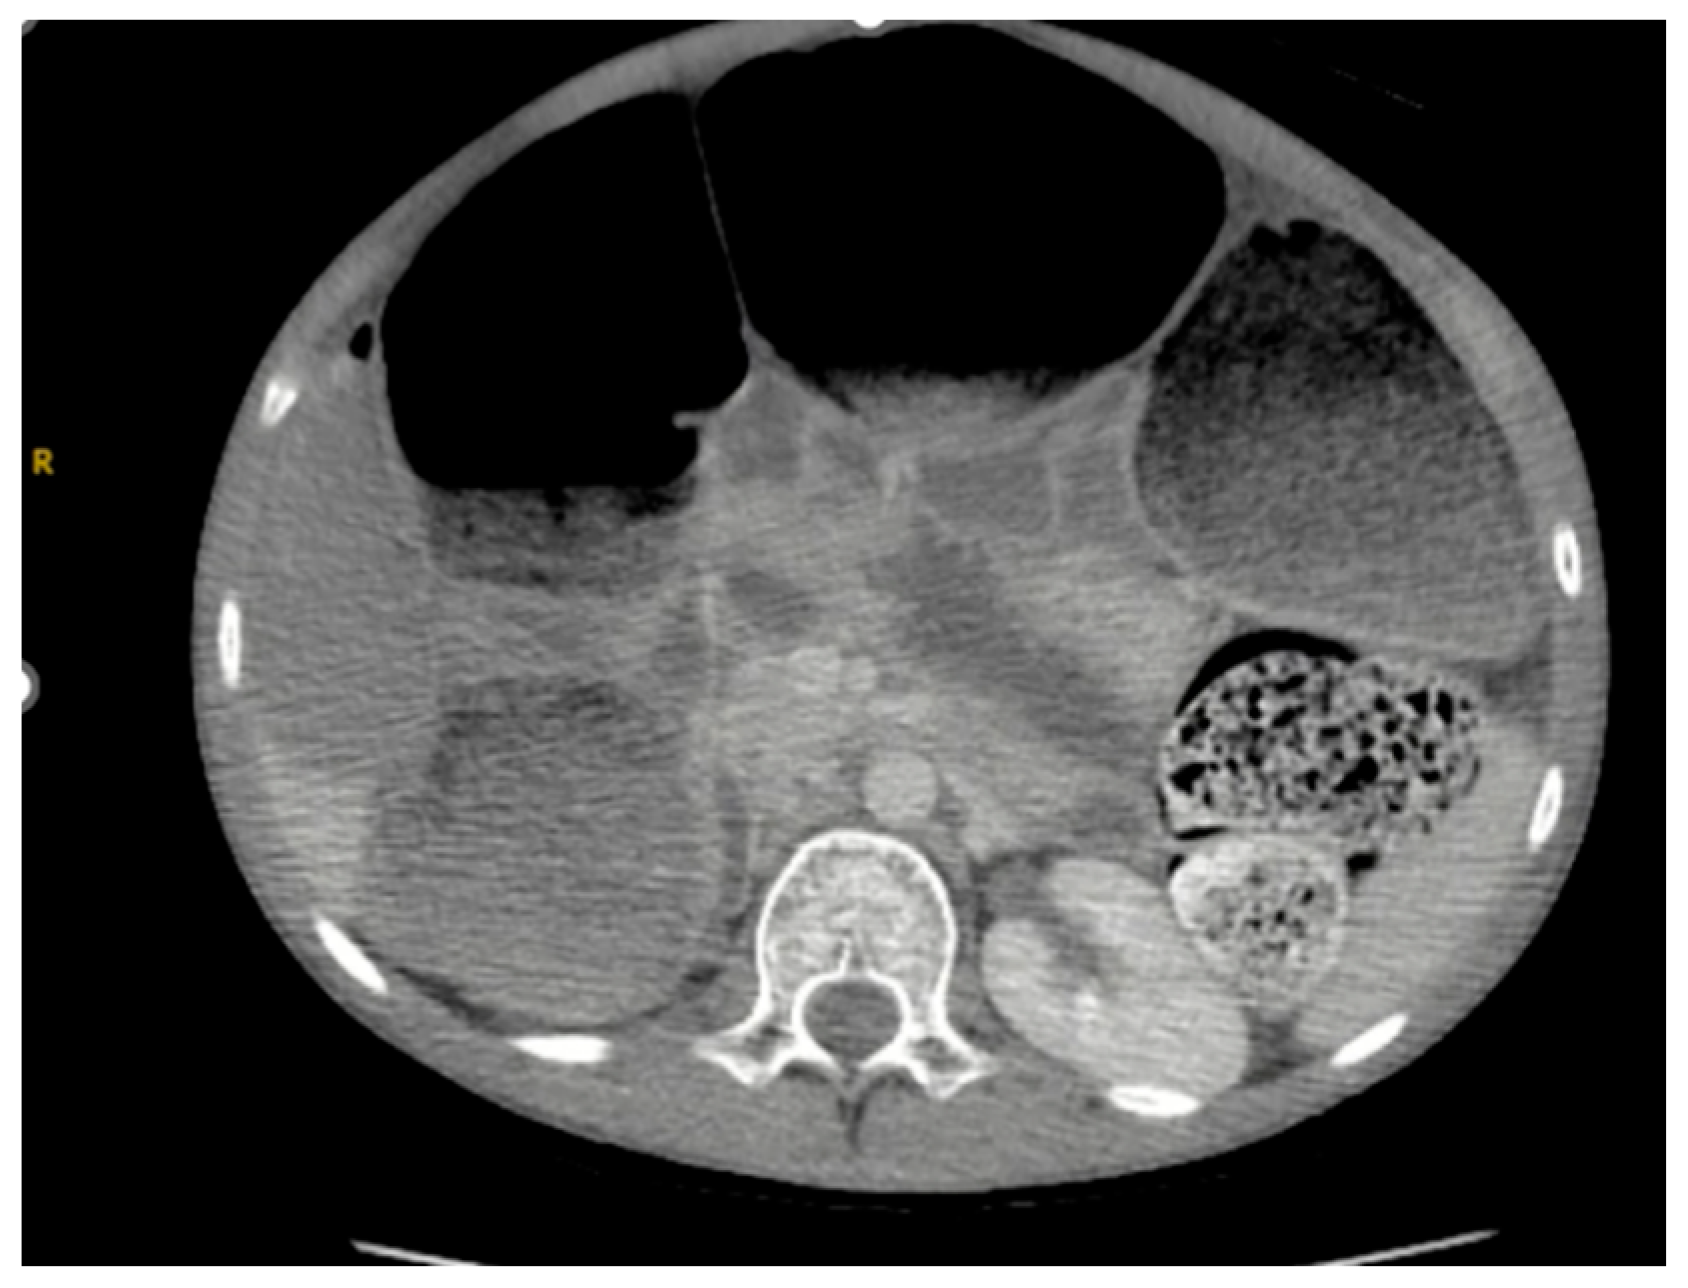

As seen in Figure 1 and Figure 2, the patient had a significantly dilated colon, measuring 6.34 cm in diameter. The patient was taken to the operating room for planned fecal disimpaction under anesthesia. The stool was too proximal to be accessed. At this point, neostigmine was administered without success. Gastroenterology was consulted intraoperatively to perform an endoscopic decompression. The colonoscopy was advanced 80 cm and revealed left-sided, thick, clay-like stool. The scope was passed beyond the stool burden, which allowed for the passage of a significant amount of air, but the abdomen continued to remain distended and tense. Due to the patient’s significant distention and concern for underlying dysmotility, an exploratory laparotomy was performed. This revealed a significantly dilated small and large bowel (Figure 3). An enterotomy was created in the distal ileum, and the stool was milked proximally through the enterotomy. Then, a loop ileostomy was created. The distal ileum was sent to pathology and revealed intramucosal ganglion cells but was otherwise inconclusive.

Figure 2. CT scan on patient presentation, revealing a colon dilated to 6.34 cm in diameter, with significant stool burden.